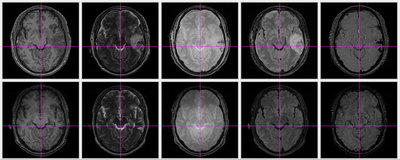

Segmentation of TBI data.

Result of coregistration